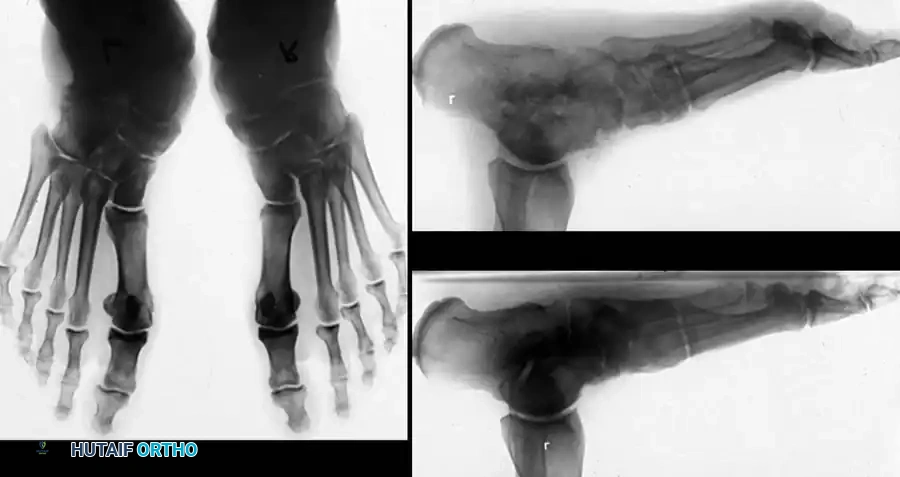

Clinical Pearl: The loss of the medial longitudinal arch can occur at the talonavicular, navicular-cuneiform, or cuneiform-metatarsal articulations. A weight-bearing lateral radiograph may initially show no bony collapse, appearing identical to the asymptomatic contralateral foot, even in the presence of obvious clinical pes planus.

- Radiography: Degenerative arthritic changes are visible in the subtalar and/or talonavicular joints.

Associated Surgical & Radiographic Imaging